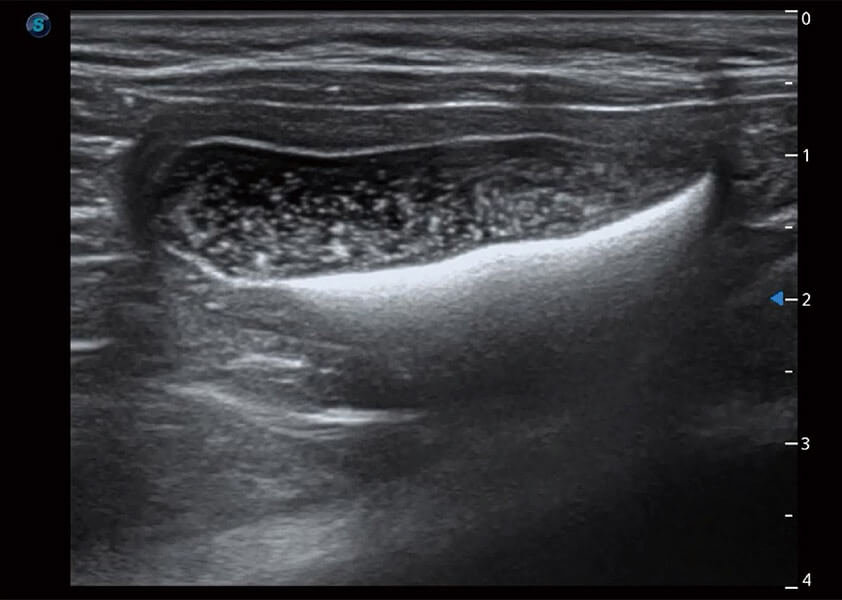

ProPet 60 作为一款高端台式动物超声设备,为动物医生的日常诊断提供了一系列贴合动物临床需求、解决临床实际问题的高级成像功能。凭借全系列高清探头,满足医生对腹部、心脏、生殖、浅表、肌骨等成像的所有需求,切实帮助您提升检查效率,提高诊断信心。

动物是人类最亲密的朋友和最值得信赖的伙伴。db真人体育官网也一直致力于探索动物专用的超声影像解决方案。 全新推出的ProPet系列,是db真人体育官网在动物超声影像智能化、专业化、精准化的一次跨越式革新。动物不能用言语来表述自己的不适,通过超声影像,ProPet系列搭建了动物医生与不同物种沟通的“桥梁”,为动物医生注入了“治愈之力”。